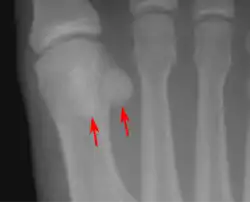

Lateral view.[10]

Bipartite medial sesamoid bone under the first metatarsophalangeal joint of the great toe of the left foot of an adult woman.

- One or both of the sesamoid bones under the first metatarsophalangeal joint (of the great toe) can be multipartite – in two or three parts (mostly bipartite – in two parts).[11]